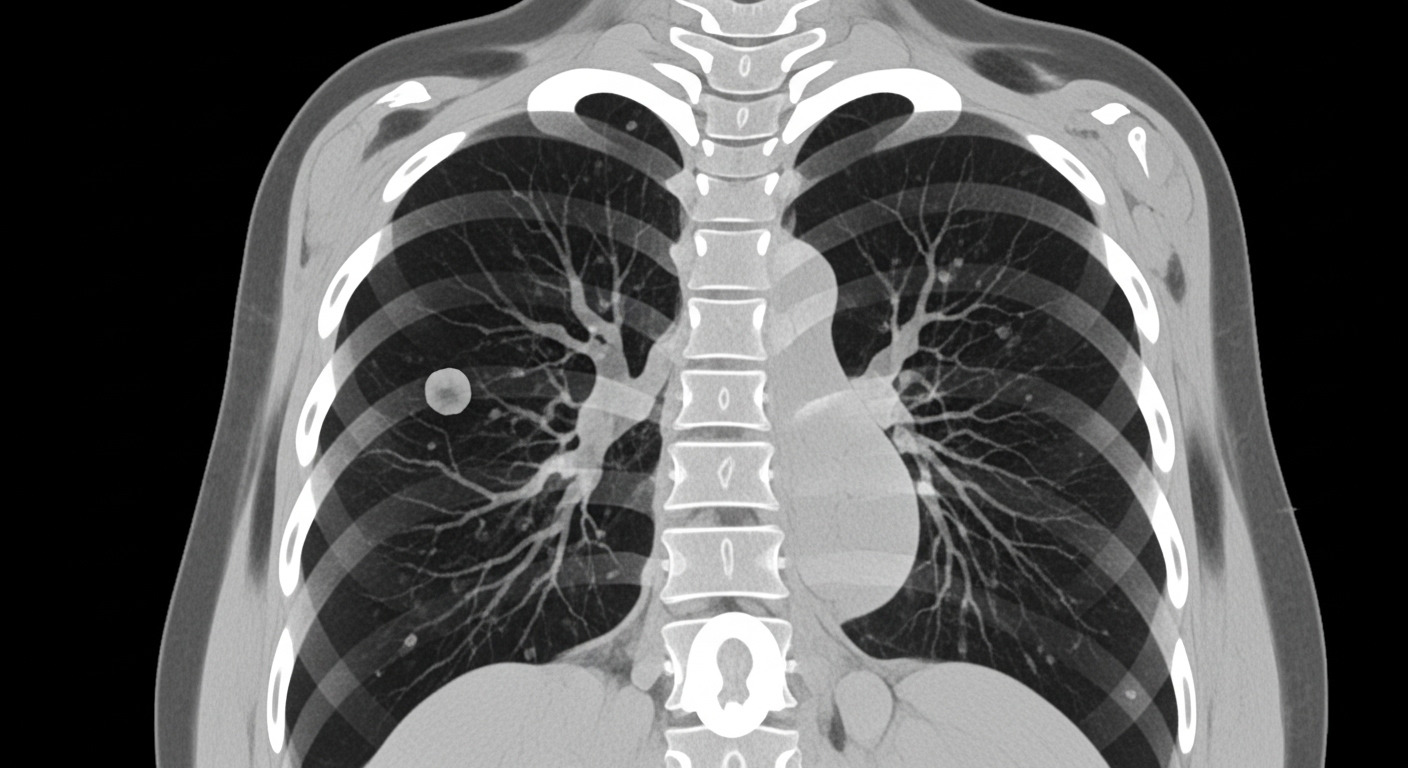

폐결절은 폐 내부에 생긴 지름 3cm 이하의 고립된 음영(덩어리)을 말합니다.

CT나 X-ray 검사에서 작은 동그라미처럼 보이며, 보통은 증상이 없습니다.

모양, 경계, 음영 정도에 따라 '고형 결절', '유리음영(GGO)', '부분 고형' 등으로 분류됩니다.